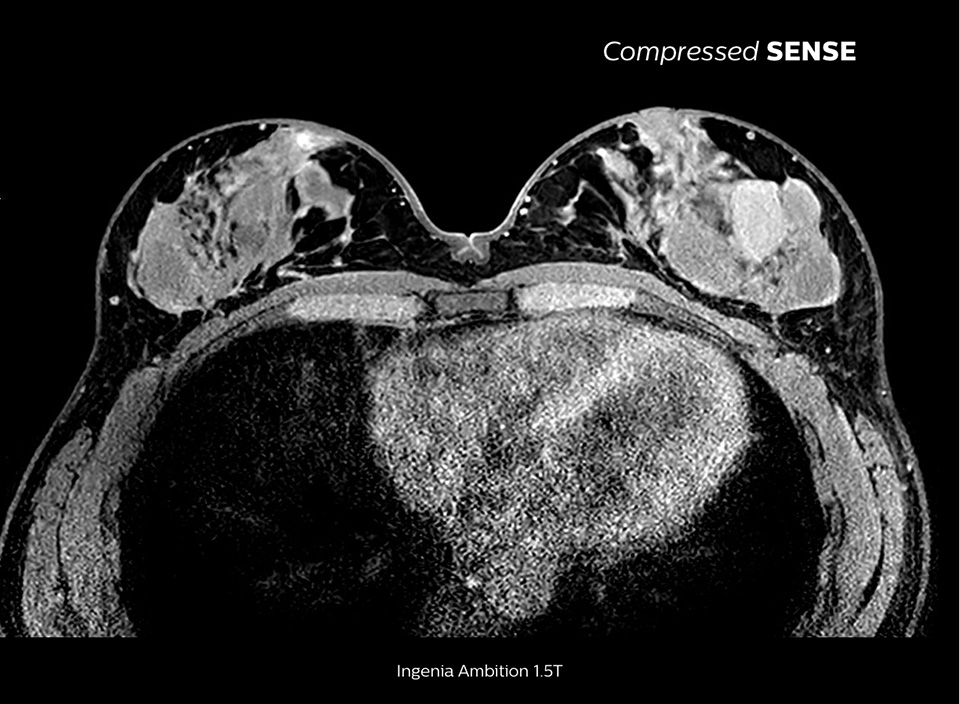

Up to 50% faster 3D sequences, with virtually equal image quality1

Compare the time savings of an MRI scan performed with Compressed SENSE MRI software versus a conventional scanning technique

High quality and fast scanning at KCH

The MRI staff at Kurashiki Central Hospital incorporated Compressed SENSE into most of the brain, spine, abdominal, and cardiac examination protocols on their Ingenia 1.5T, resulting in fast and high-quality MRI scans, which is welcomed by patients and staff.